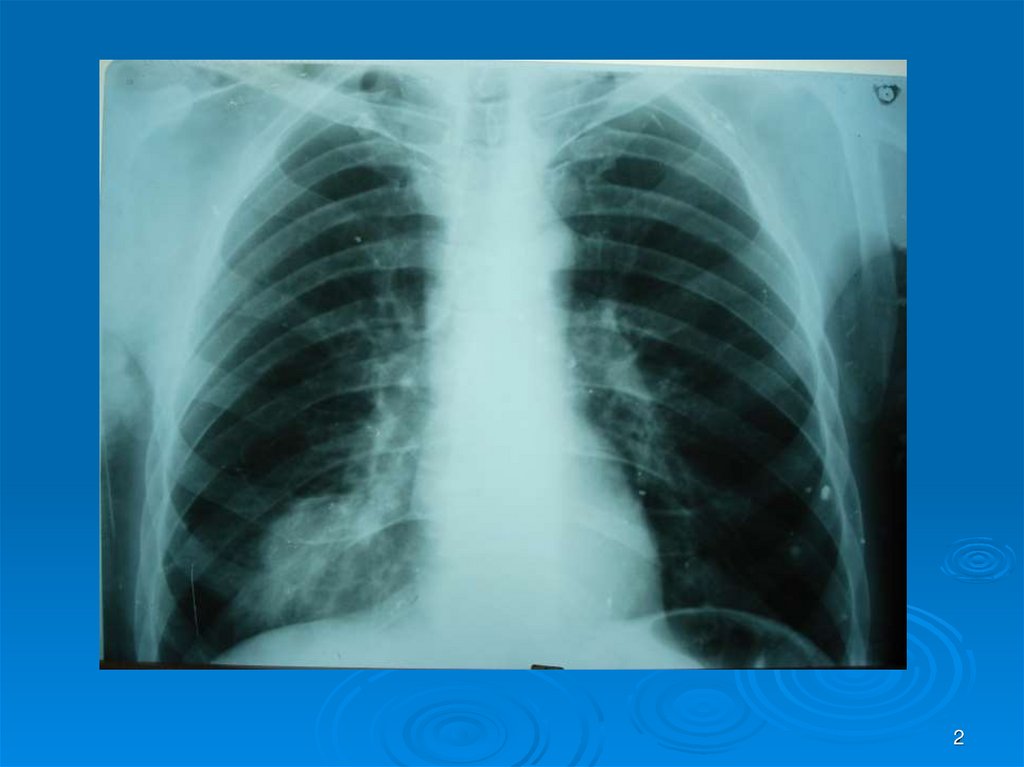

Каждый из вас должен интерпретировать Rснимки (всего 30) в ММ-презентации: назвать

заболевание, его локализацию, если осложнение

заболеваний – то указать какое. На снимках могут

быть пневмония (очаговая, сегментарная,

долевая), абсцесс легких I и II стадии, гангрена

легких, плеврит, ХОБЛ и сходные с ними болезни

легких, требующие дифференциальной

диагностики (туберкулез и др.). Успехов в работе!

2.

2